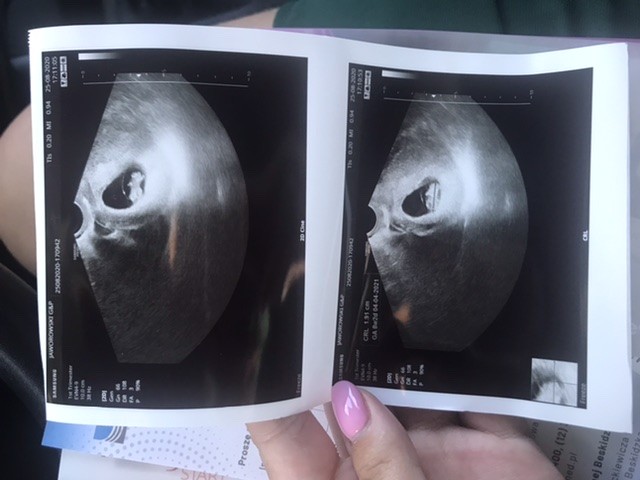

Gratulacje!!!Jest wszystko w porządku, serduszko bije ❤ Tak się cieszę ze mam ochotę rozpowiedziec całemu światuu mnie

8 + 2 tydzień![]()